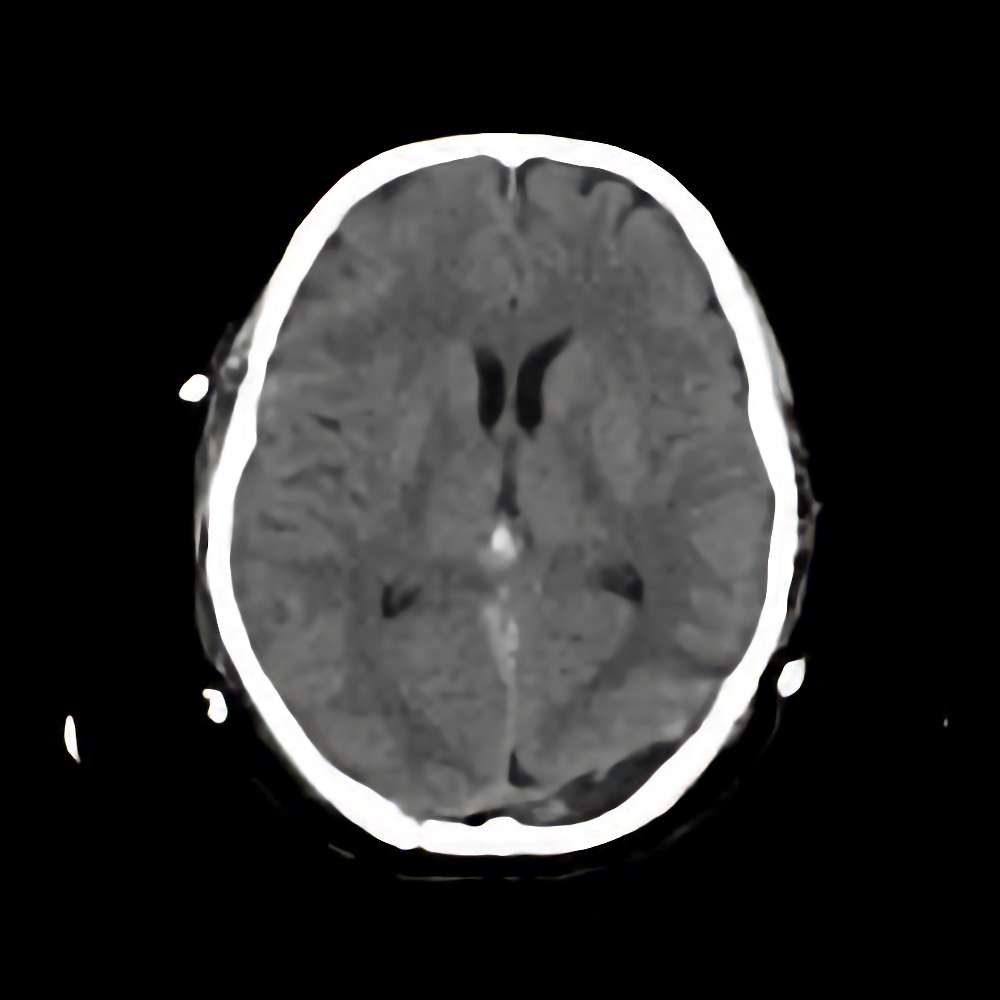

松果体腫瘍

断層撮影

手術前1

No.’14_168 手術前1

No.’14_168 手術後